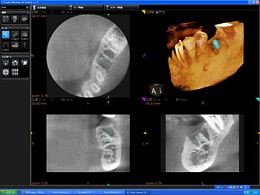

コーンビームCT

・患者様に安心安全なCT

CTとはコンピューター断層撮影装置のことですが、歯の中や骨の中を立体的に撮影し診断を行うための機器です。

インプラント治療はもとより、歯周病の診断、歯の破折、歯内療法における根管の形状や根尖の確認、埋伏歯の位置確認、外科的処置時の動脈や神経の走行状態の診断など、その応用範囲は大変大きく、様々な分野の診査診断において非常に威力を発揮します。

通常の歯科用コーンビームCTは一度に大きな部分を撮影するため、最低でも20秒~40秒以上の撮影時間が必要となるため、被曝線量がどうしても大きくなってしまいます。

当院の歯科用コーンビームCTは顎全体を1/3ずつ分割して撮影することが可能なため、11秒で撮影を完了することができます。このことにより、必要とする部位以外に不必要なX腺を照射する必要がなくなるとともに、被曝腺量を極めて少量に抑えることが可能になります。

現在アメリカなどでは過剰なCT検査による、発癌リスク上昇の危険性が指摘されおりますが、CT大国と言われる日本でも被曝線量を今後十分に考慮する必要があると考えております。